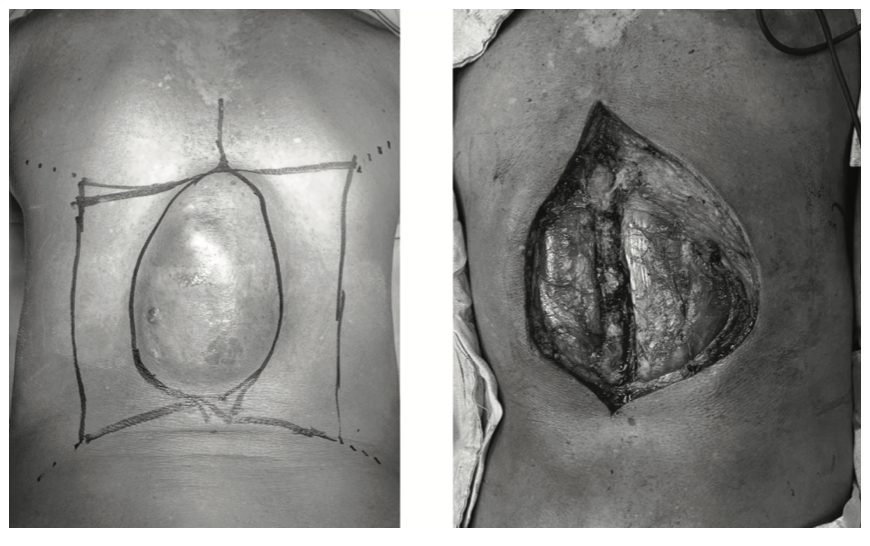

Se presenta un caso de un paciente masculino de 57 años con lesión tumoral en región dorsal de 10 años de evolu- ción. Al examen físico presenta lesión tumoral de ±15x10 centímetros, dura, poco móvil, no dolorosa a la palpación de bordes definidos (figura 1).

En un primer lugar, se diseña el tipo de colgajo a utilizar preoperatoriamente, estando el eje de los colgajos en án- gulo recto con los dermatomas. Posteriormente se reseca la lesión con márgenes amplios macroscópicamente, y se procede a realizar colgajo en piedra angular (figura 4).

Trans operatoriamente se evidencia que solo es necesa- rio realizar un lado del colgajo, ya que avanza adecuada- mente para cerrar el defecto de línea media (figura 5).